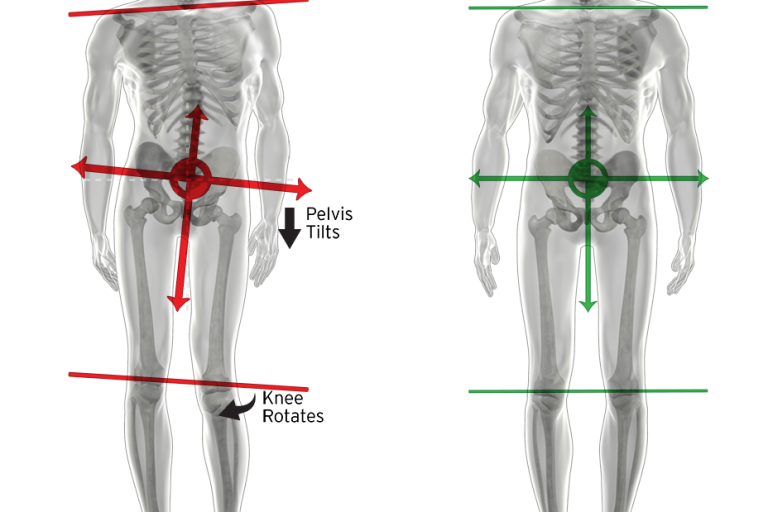

Nuestro curso miofascial es nuestra más reciente promesa formativa que busca impartir una metodología para evaluar, edificar y reprogramar la postura en función de la Biomecánica Global de las Cadenas Miofasciales. Todo esto a través del conocimiento del origen del dolor y su correspondiente estudio. ¿A quiénes va dirigida nuestra formación miofascial? Dado que…